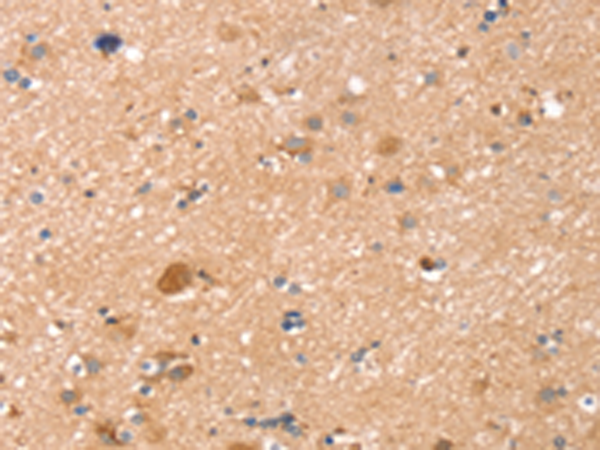

The image is immunohistochemistry of paraffin-embedded Human brain tissue using P12264(TMSB10 Antibody) at dilution 1/35. (Original magnification: ×200) |